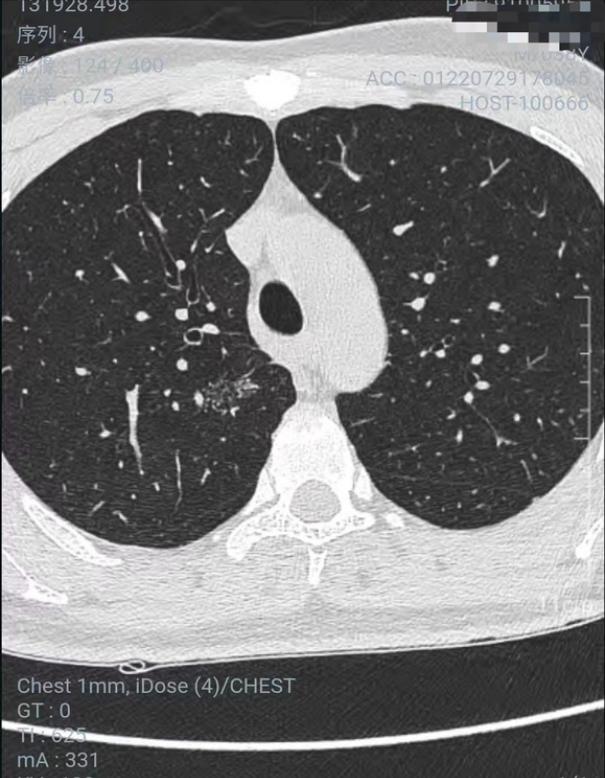

第二次复查:

吃完消炎药过了20多天后,2022年3月30日去同一家A医院复查拍CT,检查结果如下图,结节没变化。

2022年7月29日去同一家A医院复查拍CT,检查结果如下,四个月后,结节从1.2变成了1.9 cm,发现结节长这么快,真的很慌,我老公不抽烟不喝酒,身体一直比较健康,没有住过院都,也没有家族史,不知道一下就长这么大一个结节,求助各位病友,各位医生,还有敬爱的戴主任,麻烦各位有经验的帮忙看看,我们目前只看上一个北京三甲医院普通号的大夫,大夫只说磨玻璃不应该长这么快,长的挺奇怪,不典型,其他没说什么,还没挂上其他医院的号,先麻烦各位帮忙看看,万分感谢!

CT截图: